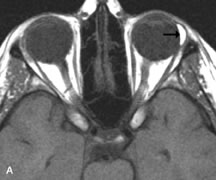

Inflammatory and Lymphoproliferative Lesions

Inflammatory conditions of the orbit, both idiopathic (inflammatory pseudotumor) and those of known causes, have been found to be hypointense to fat and isointense to muscle on Tl-weighted studies and isointense or slightly hyperintense to fat on T2-weighted images (Fig. 21).50,64,69 The more fibrous or sclerosing varieties have less signal intensity on T2-weighted images. Marked enhancement is seen in pseudotumor infiltrates after gadolinium administration.70 The same signal characteristics are demonstrated in patients with Tolosa-Hunt syndrome, with mass lesions seen in the cavernous sinuses and orbital apices.71

Fig. 21. A. T1-weighted MR scan demonstrates diffuse enlargement of both the superior rectus and levator palpebrae superioris muscles (single arrows). The involvement of the tendinous insertions and preseptal soft tissues (open arrows) as well as lack of involvement of other muscles helps differentiate this entity from thyroid-associated orbitopathy. B and C. Postcontrast fat-suppressed T1-weighted MR scans demonstrate extensive enhancement of the involved muscles as well as the preseptal (open arrows) and perinuscular tissues (double arrows).